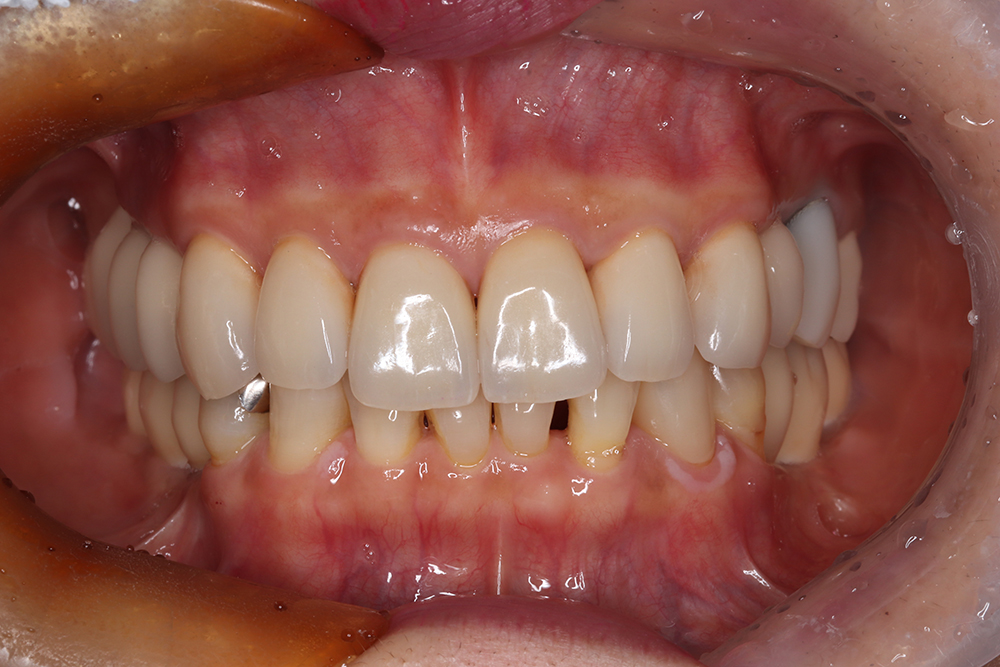

55歳 男性

- 主訴

- 前歯でしか咬めなく、食事を採るのに非常に困難で辛い

- 処置内容

- 上顎6本、下顎3本

- 治療費用

- 上顎:約230万(税込)下顎:約120万(税込)

- 治療期間

- 上顎:1年(仮歯まで8か月)下顎:8か月(仮歯まで5か月)

- リスク

- 上部構造物、仮歯の破折、術後の腫れ(3日)、人工歯根脱落リスクがあります